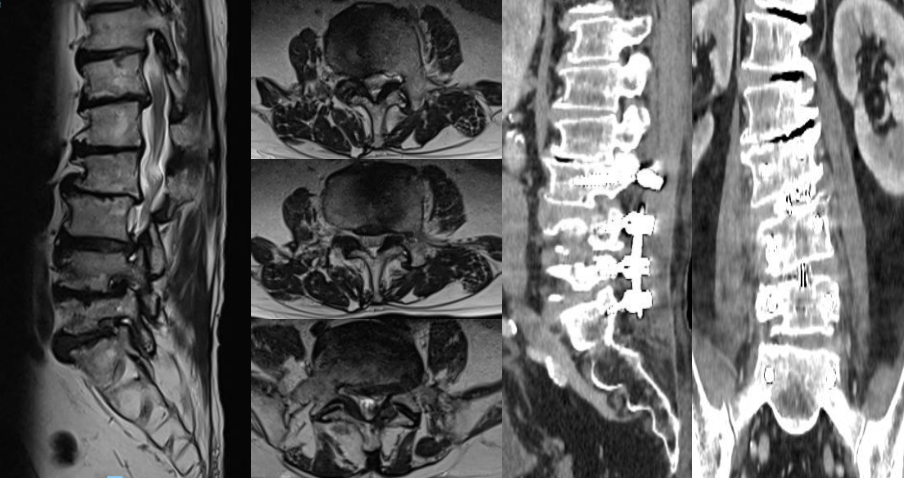

Hình 2. Cộng hưởng từ cột sống trước phẫu thuật với hẹp ống sống đa tầng từ L3-S1, và hình ảnh cắt lớp vi tính sau phẫu thuật với phương tiện KHX L3L4L5S1 đúng vị trí